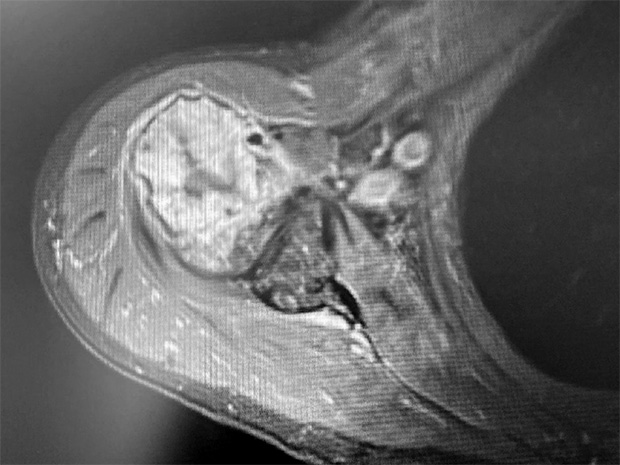

Pre-op

Picture 3 and 4: X-ray m-l and MRI

Patient:

- 73 year old male with bone tumor in the proximal humerus right side